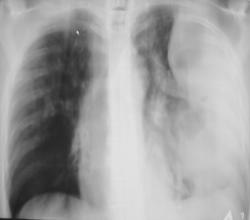

Пациент мужчина преклонного возраста в «критическом состоянии» доставлен машиной скорой помощи «прямо в рентгеновский кабинет». Температура, разлитые сильные боли слева в грудной клетке, интоксикация. Сделана рентгенограмма только в прямой стандартной проекции (иллюстрация 1). Решено назначить противовоспалительную и дезинтоксинационную терапию и после улучшения состояния провести рентгенологическое исследование. Через 1 неделю пациенту субъективно «стало лучше» доставлен в рентгеновский кабинет.